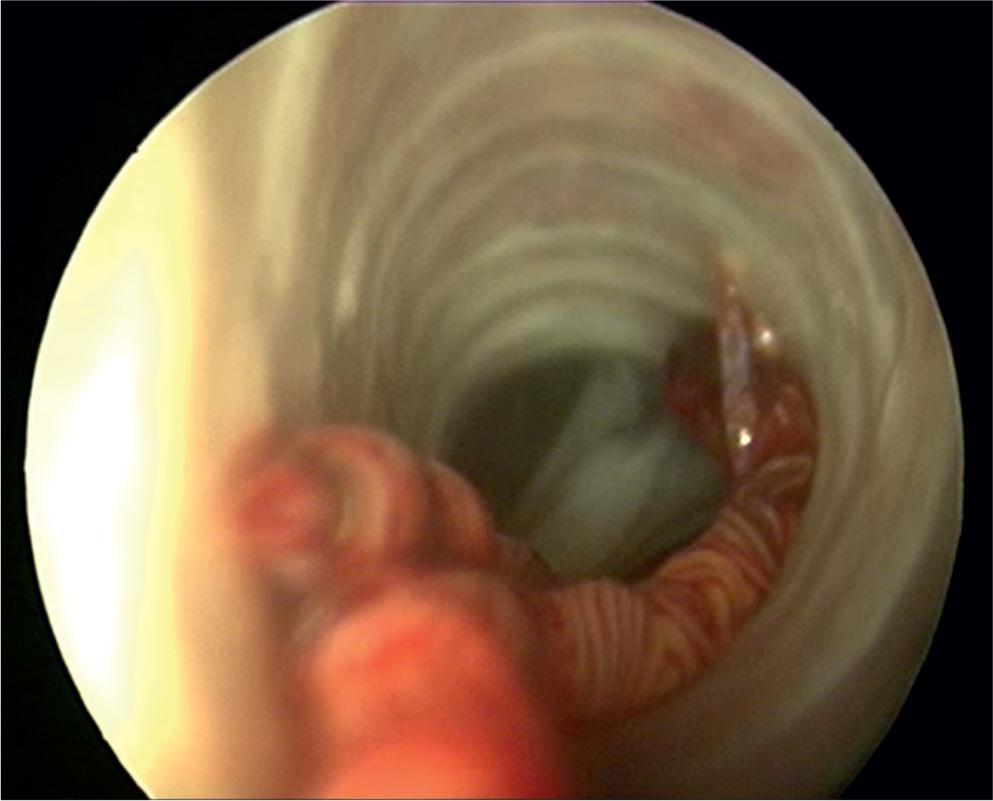

A parasitological necropsy of a bird involves a detailed post-mortem examination to identify internal and external parasites. In short, the process begins with external examination for lesions or discharges, followed by incisions to the body cavity to assess internal organs, air sacs, and the gastrointestinal tract for parasites, abnormalities, and changes in tissue consistency, size, or color. Samples of organs and contents are collected for further analysis, including microscopic examination for parasites (Van Riper, 1980). Figures 1 – 2 show the trachea in situ, highlighting the presence of S. trachea within its structure. Figure 3 illustrates infectious larvae L3 encysted in the earthworm’s body wall.

Adult gapeworms fi xed in lower part of trachea, bifurcation seen.

Short-term inhalant anesthesia with isoflurane was applied to the birds in individual groups to examine the trachea. Tracheoscopy to the level of the syrinx was possible in medium- to large-sized birds using a 180 mm long, 2.7 mm endoscope. Visualization could be improved by extending the pheasant neck (Murray et al., 1999). Simultaneously, the blood was withdrawn from the jugular vein.